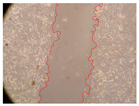

| Representative Image of the Cells at the Initial Moment (0 h) | ||||

|---|---|---|---|---|

![]() | ||||

| 2 h | 8 h | 12 h | 24 h | |

| Control | ![]() | ![]() | ![]() | ![]() |